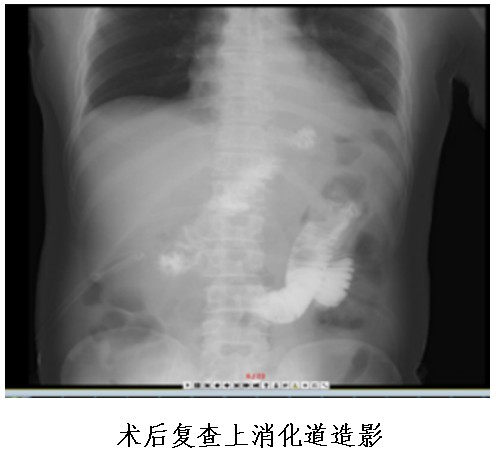

普外中心主任兼胃腸外科主任譚曙光組織醫(yī)師團隊就患者治療方案進行討論,認為該名胃體神經(jīng)內(nèi)分泌瘤患者,符合手術(shù)指征。經(jīng)過反復(fù)評估并與患者本人及家屬溝通,最終譚曙光醫(yī)師團隊決定摒棄傳統(tǒng)的胃切除術(shù),選擇腹腔鏡根治性近端胃切除+D2淋巴結(jié)清掃及雙通道吻合(食道空腸over-Lap吻合及空腸遠端胃吻合)術(shù),有效減少了反流性食道炎等術(shù)后并發(fā)癥的發(fā)生。1月9日,患者完成了手術(shù),術(shù)后恢復(fù)順利并于22日出院。

據(jù)悉,腹腔鏡根治性近端胃切除+D2淋巴結(jié)清掃及雙通道吻合(食道空腸over-Lap吻合及空腸遠端胃吻合)術(shù),屬于腹腔鏡下IV級高難度手術(shù)。該手術(shù)的優(yōu)點為全部操作均在腹腔鏡下完成,對腹腔干擾少,術(shù)后切口疼痛及腸粘連發(fā)生率明顯減少;能完整切除胃部病灶,最大限度地保留患者的正常胃組織及功能;能大大減少胃切除術(shù)后的嚴(yán)重的胃食管反流性疾病等并發(fā)癥的發(fā)生幾率。

①食管空腸吻合口;

②殘胃空腸吻合口;

③空腸空腸吻合口。

其中,食管空腸吻合口距殘胃空腸吻合口15-20cm,殘胃空腸吻合口距空腸空腸吻合口15—20cm。

食物通過食管空腸吻合口后,一部分通過胃空腸吻合口進入遠端胃、十二指腸及小腸,另一部分食物直接進入小腸,故稱之為“雙通道”消化道重建。

該吻合方式通過增加了一個殘胃與小腸的食物通道,可以防止胃酸直接反流進入食管,而遠端胃和原有消化通道的保留,可以維持胃與十二指腸的部分功能,成功解決近端胃切除術(shù)后患者胃食管返流、胃癱及遠期營養(yǎng)障礙的問題,大大提高術(shù)后患者的生活質(zhì)量。